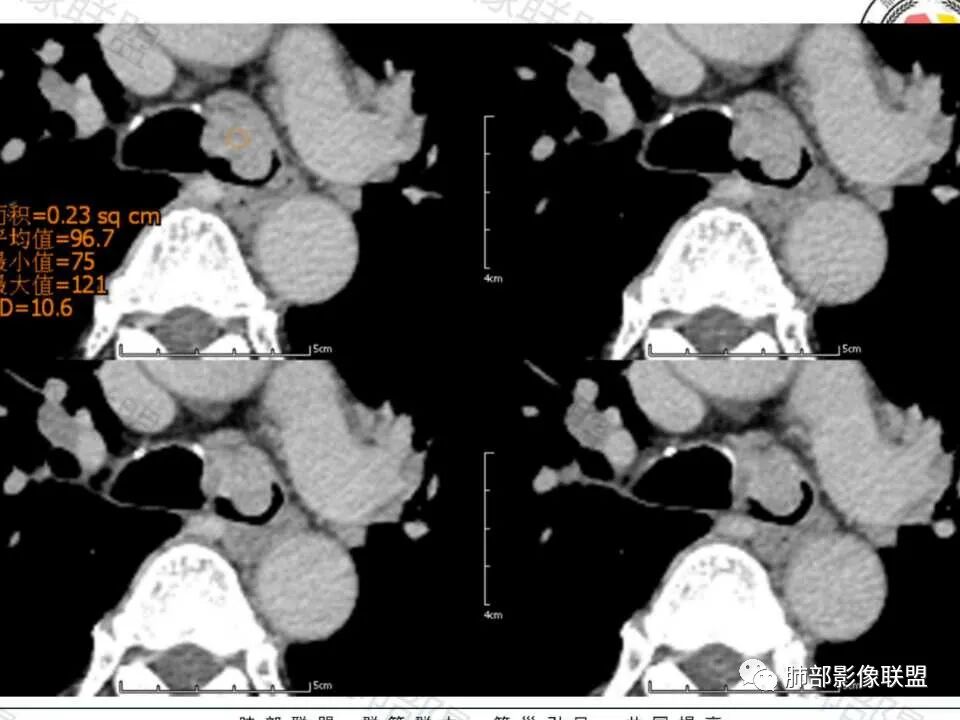

晨读57岁的男性病人,病史一周,以咳嗽咳痰痰中带血为主要表现, CT扫描与支气管分叉偏左侧支气管的位置上见分叶状的一个结节影,并局部凸向管腔内,支气管管腔明显的变窄, 病灶以实性为主,周围斑点状的钙化,生长支气管内外侧壁,可见“冰山征”,增强扫描比较明显的强化,肿块未见坏死,周围无明显肿大淋巴结。考虑支气管来源的占位。类癌?鳞状细胞癌?鉴别:支气管息肉?硬化性血管瘤?

49.8-93.6-102.4 气管软骨侵蚀,匍匐生长,菜花,淋巴结多、大。

二、影像表现:肿瘤好发于气管后壁软骨和膜部连接处,这与该部位黏液腺较多有关,沿气管粘膜下延伸,呈腔内息肉样或宽基底的软组织密度肿块,沿管壁梭形生长,长径大于短径(具有粘膜下浸润生长的特性所致),管壁弥漫或全周增厚,伴管腔不同程度狭窄,肿瘤可同时侵犯腔内外,形成腔内外软组织肿块。平扫密度均匀,呈软组织密度,瘤内坏死钙化少见。增强后病灶呈不同程度均匀或不均匀轻中度强化,肺内转移常见。